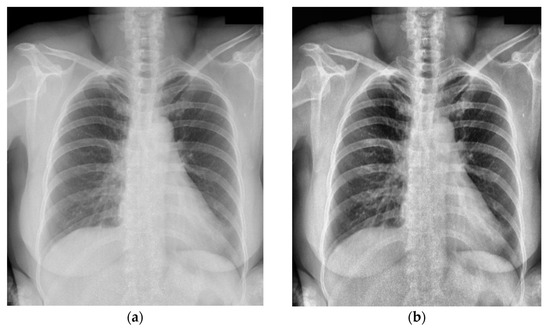

Figure 5.

The pre-processing for label box: (a) original label in the VinDr-CXR dataset; (b) optimized annotation result obtained using WBF. The red box indicates the location of the chest abnormality.

Figure 6.

The image pre-processing with histogram equalization: (a) original image in the VinDr-CXR dataset; (b) pre-processing result using histogram equalization.